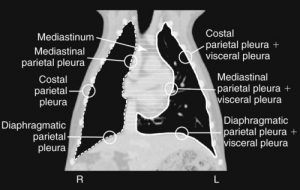

To understand what are thymoma, you need to have a basic understanding of the anatomy of the chest. The chest or thoracic cavity has different components. Obviously, we have the rib cage, the lungs, and the heart. The mediastinum is a potential space found in the midline of the thoracic cavity that divides it into two halves. There is a front part called the cranial mediastinum, a middle part, and a back part called the caudal mediastinum.

Image Credit: Veterian Key

The cranial mediastinum is the area on midline in front of the heart. This part contains the esophagus (food pipe), trachea (windpipe), and the thymus. The thymus is a small glandular organ that is a site of production and maturation of special immune system cells called T lymphocytes. This organ is very active in utero and during adolescence but regresses or involutes with age. A thymoma is a cancer arising from cells of the thymus gland called thymic epithelia.